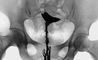

Исследование чаще проводят на 7—19-й день после окончания менструации в положении женщины для гинекологического исследования. После обработки влагалища и шейки матки спиртовым раствором йода в канал шейки матки вводят маточную канюлю, через которую в полость матки медленны под контролем рентгеноскопии вводят 10—12 мл 60—76% раствора водорастворимого рентгеноконтрастного вещества (урографина, уротраста, гипака и др.), температура которого равна 36—37°. По мере заполнения полости матки и маточных труб производят рентгенографию. Если на рентгенограммах через 3—5 мин не отмечается заполнения маточных труб, через 20—25 мин делают повторные снимки. По рентгенограммам оценивают состояние канала шейки матки, положение матки, конфигурацию и размер ее полости, расположение и проходимость маточных труб (рис. 1 и 2).